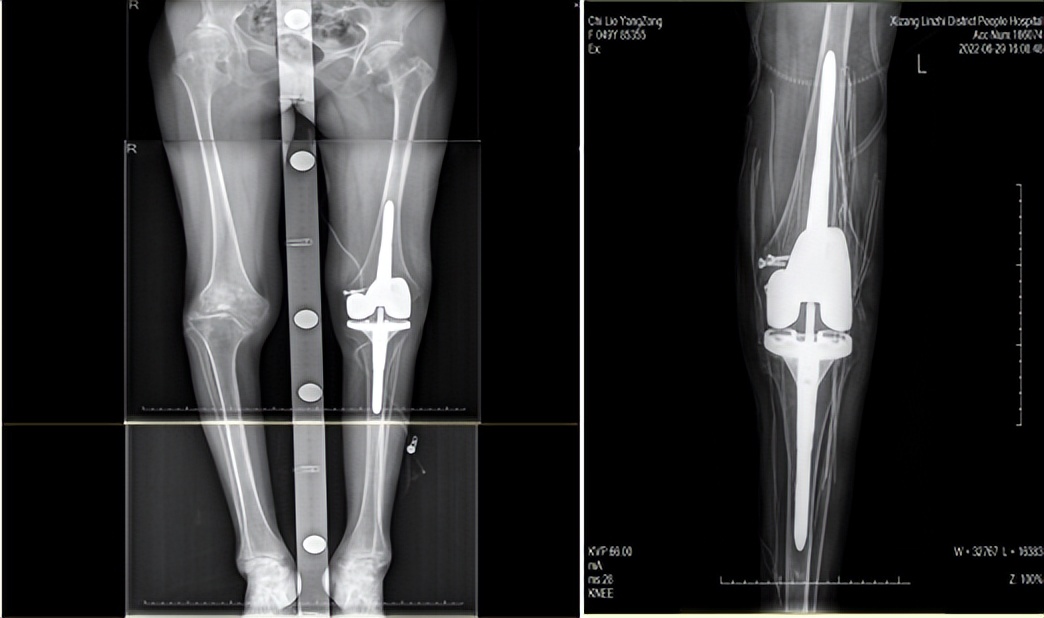

▲“顺风腿”-右膝关节内翻,左膝关节外翻;左侧股骨远端发育不良,局部骨缺损

入院后对患者进行详细的体格检查,患者身高145cm,体重42.5kg,营养不良并伴有贫血。双膝畸形严重,右侧膝关节内翻(内翻20度),左侧膝关节外翻(外翻27度),是我们常说的“顺风腿”,双侧膝关节周围压痛明显,膝关节活动范围10-90°。术前X光片示:右侧膝关节内翻畸形,内侧平台缺损严重,左侧膝关节外翻畸形,左侧股骨远端发育不良。经科室讨论及评估,认为其双膝关节骨性关节炎严重,目前左侧症状严重,严重影响其生活,建议行左侧人工全膝关节置换手术,从而缓解膝关节疼痛,改善膝关节功能,提高生活质量。

手术显露进入膝关节后,首先进行髂胫束的松解,应用“outside-in”技术,矫正15°以内的伸直位外翻畸形。术中同时也证实了术前的判断,股骨远端外侧明显发育不良,截骨后股骨远端外侧及后侧出现明显的骨缺损,根据术中截骨后骨缺损情况,深度约8mm,股骨后髁内外侧缺损约4mm,综合考虑患者的情况,术中选择使用了垫块和生物型延长杆,同时术中发现患者骨质疏松严重,内侧副韧带止点轻度撕脱,予以使用螺钉加强固定,术后针对患者个体情况制定个性化的康复锻炼方案,在支具保护下指导患者下地负重锻炼。复查X光片示,假体位置满意,对位对线好,左侧股骨外侧及后侧骨缺损采用金属垫块固定良好。现患者疼痛缓解明显,功能恢复满意。

▲术后左下肢外翻畸形明显矫正,假体位置安装精准